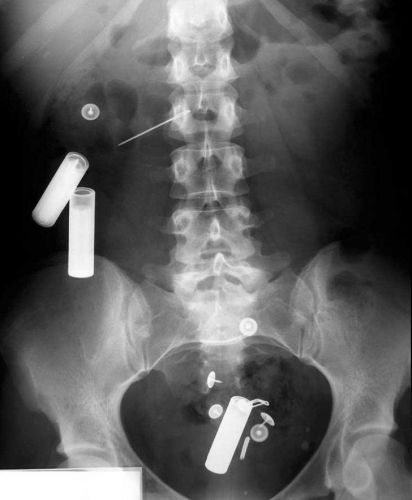

Os objetos mais BIZARROS encontrados no ânus pelos médicos

Linha e agulha